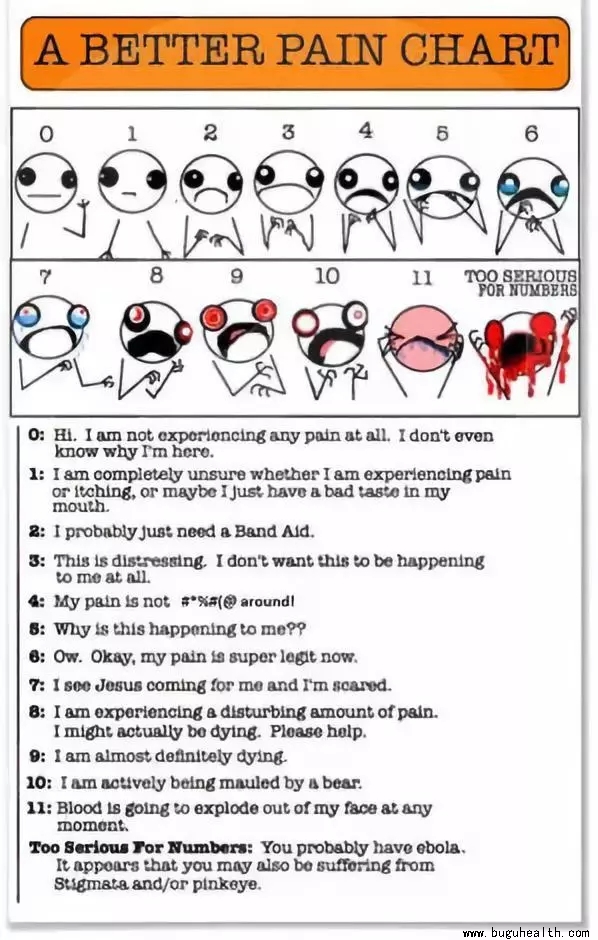

- 布骨医学科普:跑步时出现疼痛,我还可以跑吗?看一位资深PT是怎么说得。 布骨康复医疗中心 ,2021-11-29

- 我并非追求患者百分之百无痛的超级粉。绝大多数的疼痛患者,其影响因素是多方面的,任何一方面都有可能触发疼痛。我通常会很直接的告诉患者,我们并不寻求运动过程中的完全无痛。如果仍有20%的疼痛,我倒认为这是一个给患者改善机会的绝好观察窗口。这实际是一种体验式学习,随着时间的推移,当人们看到疼痛的百分比一次.....